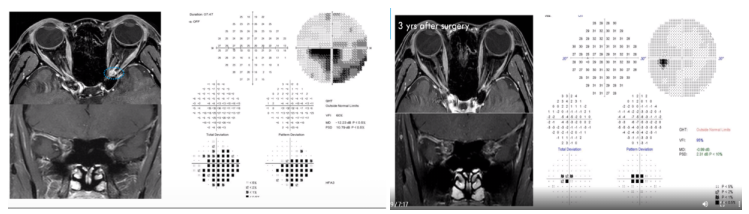

案例分享:37岁女性患者,左眼视力丧失2个月。对高剂量IV甾体类药物治疗无效。眼科检查:视力:右1.0 左CF/30cm。EOM:WNL。左眼RAPD(+)。影像学检查见下图(左)。经鼻内窥镜肿瘤切除术后3年,治疗效果见下图(右)。